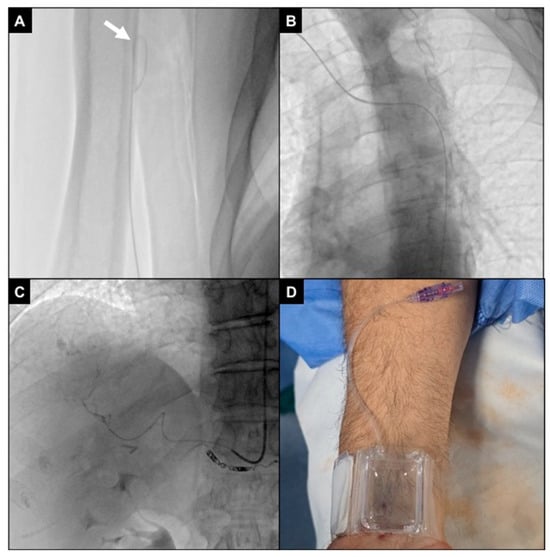

2.4. Procedures

- Iezzi, R.; Posa, A.; Contegiacomo, A.; Maresca, A.; Rodolfino, E.; Merlino, B.; Bilhim, T.; Guimaraes, M. Application and Validation of a transRADial Access Score (RAD-Access) in Patient Selection for Safe Radial Access in Liver Cancer Intra-Arterial Procedures. Cancers 2025, 17, 1385. [Google Scholar] [CrossRef]

- Gayed, A.; Yamada, R.; Bhatia, S.; Fischman, A.; Heran, M.K.S.; Himes, E.A.; Klass, D.; Patel, S.; Schiro, B.J.; Walker, T.G.; et al. Society of interventional radiology quality improvement standards on radial artery access. J. Vasc. Interv. Radiol. 2021, 32, 761.e1–761.e21. [Google Scholar] [CrossRef]